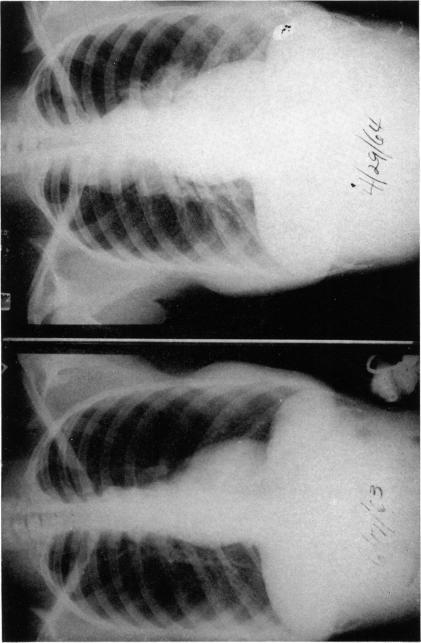

Diagnosis and treatment of uveitis in association with sarcoidosis.

Trans Am Ophthalmol Soc. 1968;66:117-41.